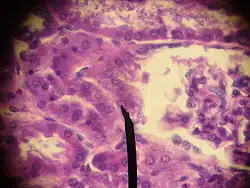

Юкстагломерулярные клетки (известные также как гранулярные клетки — за огромное количество гранул в цитоплазме) в почке отвечают за синтез, хранение и секрецию фермента ренина, а также эритропоэтина. Выброс ренина происходит в ответ на различные сигналы: стимуляция адреналином, уменьшение абсорбации хлорида натрия, а также уменьшение кровяного давления в клубочке.

Юкстагломерулярные клетки являются специализированными клетками гладкой мускулатуры, утратившей способность к сокращению, и находятся в стенке приносящей артериолы. Характерной особенностью юкстагломерулоцитов является большое количество структурно-гетерогенных секреторных гранул в их цитоплазме. Гранулы контактируют с эндоплазматическим ретикулумом, митохондриями и ядром. Все гранулы ограничены одинарной мембраной, но различаются по своей внутренней структуре. По этому признаку можно выделить три типа гранул:

Полиморфизм различных типов гранул отражает основные фазы секреторного цикла в образовании юкстагломерулярными клетками фермента ренина.